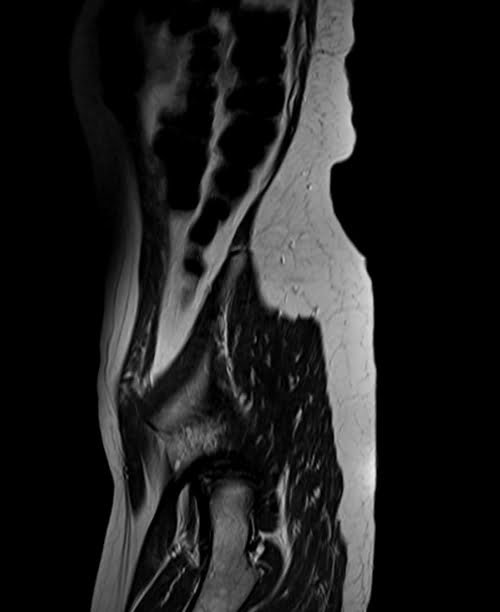

mri lumbosacral plexus sagittal t2 image 4 - MRI